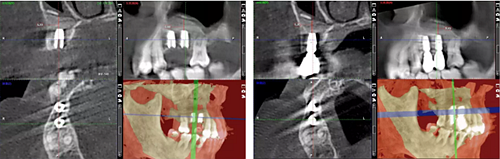

術(shù)后13個月

術(shù)后14個月

從組織學(xué)上看,植入早期并未出現(xiàn)大量炎性細(xì)胞浸潤,表明材料的組織相容性較好并能有效地發(fā)揮支架作用。β-TCP同時具有大孔兼微孔結(jié)構(gòu),微孔結(jié)構(gòu)對于材料的生物可吸收性具有重要影響,有利于組織的滲入,形成局部酸性環(huán)境,促進(jìn)材料的降解;而大孔結(jié)構(gòu)則有利于發(fā)揮材料的骨傳導(dǎo)性,較大的表面積可促進(jìn)材料在體內(nèi)的降解。同時材料的微孔結(jié)構(gòu)也有利于骨組織的長入,對材料的早期固定和骨缺損修復(fù)提供了有益的物理結(jié)構(gòu)。

隨著間充質(zhì)細(xì)胞的長入,β-TCP逐漸被分割包圍,有血管形成和吞噬細(xì)胞浸潤,β-TCP開始降解,為新生骨的形成進(jìn)一步提供空間,最終修復(fù)骨缺損。